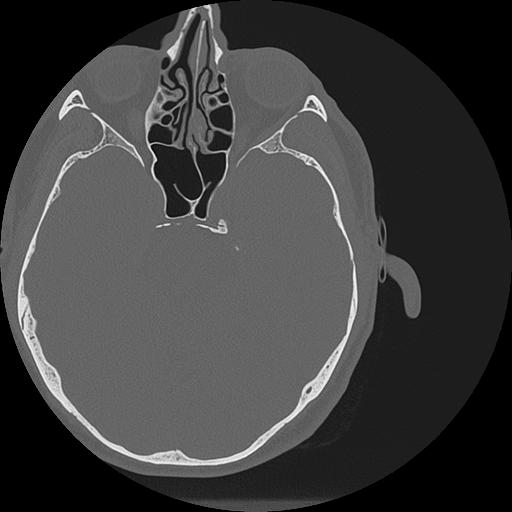

7 HUESO,,Vol,0.5,HUESO,,